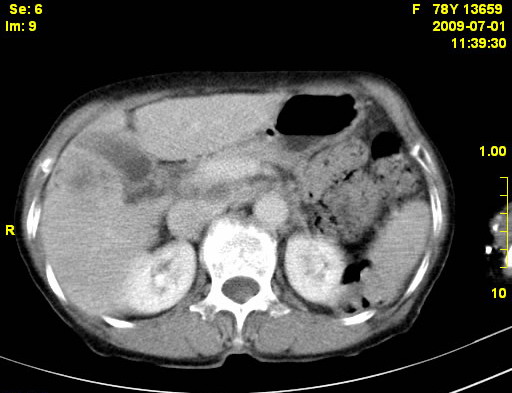

以下是引用zjzjr在2009-7-3 11:02:00的发言:[br]动脉期不均匀强化,门脉期及延迟期强化明显,肝门部见肿大淋巴结影,肝内胆管扩张.考虑肝右叶前段胆管细胞癌伴肝门淋巴结转移,胆内胆管扩张.慢性胆囊炎.

以下是引用dsl555在2009-7-4 10:59:00的发言:[br]考虑肝右叶前段胆管细胞癌伴肝门淋巴结转移,胆内胆管扩张.慢性胆囊炎. [br][br]支持。